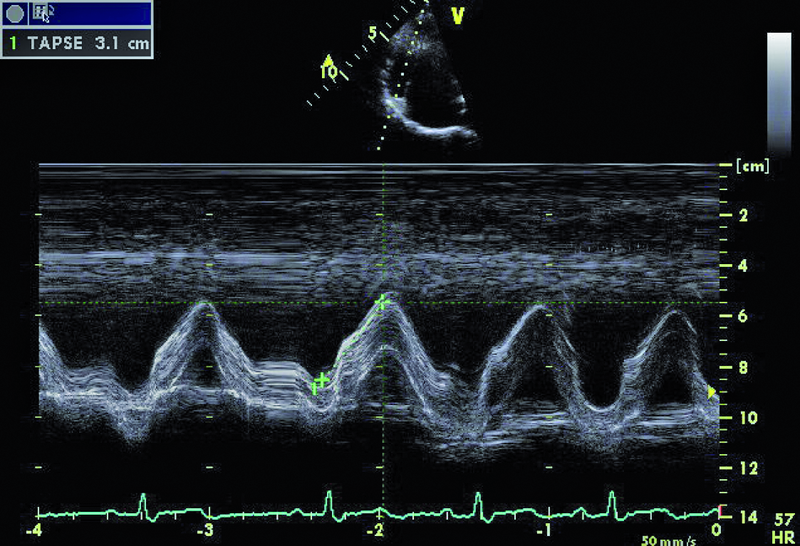

Cechy anomalii Ebsteina łatwo zidentyfikować. Należy zwrócić uwagę na odległość między przyczepem płatka przegrodowego zastawki trójdzielnej a przyczepem przedniego płatka zastawki mitralnej (ryc. 1). Fizjologiczne przesunięcie płatków jest niewielkie i zwykle nie przekracza 5-10 mm. Za kryterium rozpoznania anomalii uważa się wartość 20 mm (w przedstawionym przypadku 50 mm). Przemieszczone płatki są zwykle zmienione organicznie, pogrubiałe, często pociągane przez struny ścięgniste. Płatek przedni jest prawidłowo przyczepiony do pierścienia zastawki trójdzielnej, natomiast jest zwykle powiększony i kształtem może przypominać żagiel (ryc. 1-3). Cechą płatka przedniego w anomalii Ebsteina jest także jego nadmierna ruchomość i liczne perforacje powodujące zwykle więcej niż jedną falę zwrotną (ryc. 4). Zatrializowana część prawej komory znajduje się między przemieszczonymi przyczepami płatków przegrodowego i tylnego, a właściwa jama ma zmniejszoną pojemność. To, czy wada daje objawy, zależy od nasilenia niedomykalności trójdzielnej i od współistniejących anomalii. Niedomykalność trójdzielna u tego pacjenta, mimo dużego przemieszczenia płatka przegrodowego, była mała (ryc. 4). Zarejestrowany metodą doplerowską profil prędkości z jednego ze strumieni niedomykalności wskazywał na niepodwyższone ciśnienie w jamie prawej komory (ryc. 5). Funkcja mięśnia prawej komory określona za pomocą pomiaru przemieszczenia bocznej części pierścienia zastawki trójdzielnej była prawidłowa (ryc. 6). Diagnostykę można na tym etapie zakończyć i uznać, że chory kwalifikuje się do dalszej obserwacji. Badanie przezprzełykowe jest potrzebne u pacjentów, u których nie można ocenić dokładnie morfologii zastawki trójdzielnej. Może też być konieczne w przypadku desaturacji krwi tętniczej i podejrzenia często towarzyszącego anomalii ubytku przegrody międzyprzedsionkowej. Warto zaznaczyć, że ubytek zwykle charakteryzuje się przeciekiem prawo-lewym, na skutek dysfunkcji jam prawego serca i wzrostu ciśnienia w jamie prawego przedsionka. W tym przypadku, wobec braku sinicy, badania przezprzełykowego nie wykonano. Cewnikowanie serca także nie jest konieczne, ponieważ chory ma małą niedomykalność trójdzielną i dobrą wydolność fizyczną, a więc nie kwalifikuje się do leczenia operacyjnego.